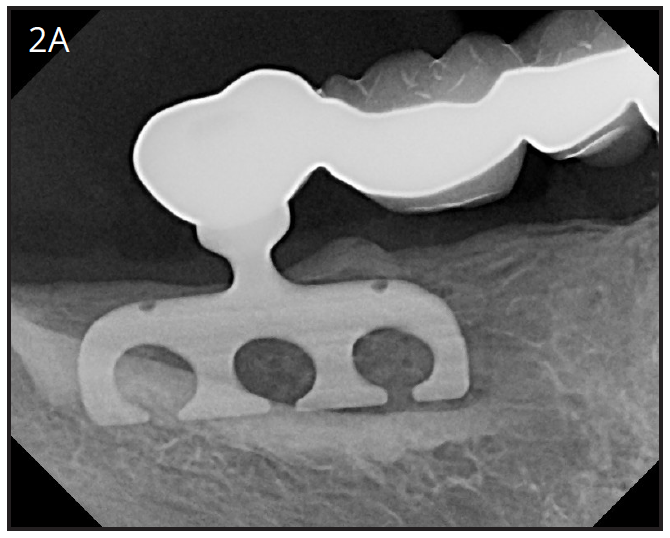

In 1966, Dr. Linkow presented the blade implant around the same time the transosseous implant was published.7 This was the first endosseous implant.(Figures 2A, 2B) This implant is inserted in the jaw by making a groove inside the jaw bone from the oral cavity. One or several posts area attached to the fin shaped plate, which anchors the restoration. The success rate for this implant was under 50%, and is no longer used today.8,9 The problem with it was that it got loose and infected eventually, and had to be removed.

Figure 2A – Blade implant design

Figure 2A